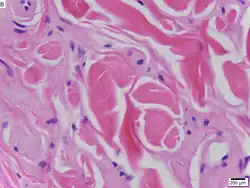

La maladie est causée par des mutations type perte de fonction du gène de la protéine de la matrice extracellulaire 1 (ECM1)[7] localisé sur le chromosome 1 en 1q21. Les symptômes dermatologiques sont causés par l'accumulation d'un matériau hyalin dans le derme et l'épaississement de la membrane basale de la peau[4]. La maladie de Urbach-Wiethe est généralement diagnostiquée par ses manifestations cliniques dermatologiques, en particulier les papules perlées sur les paupières. La découverte des mutations du gène ECM1 a permis l'utilisation de tests génétiques pour confirmer un premier diagnostic clinique. La coloration acide periodique-Schiff (PAS) et l'immunohistochimie peuvent également être utilisées pour le diagnostic[3],[8].